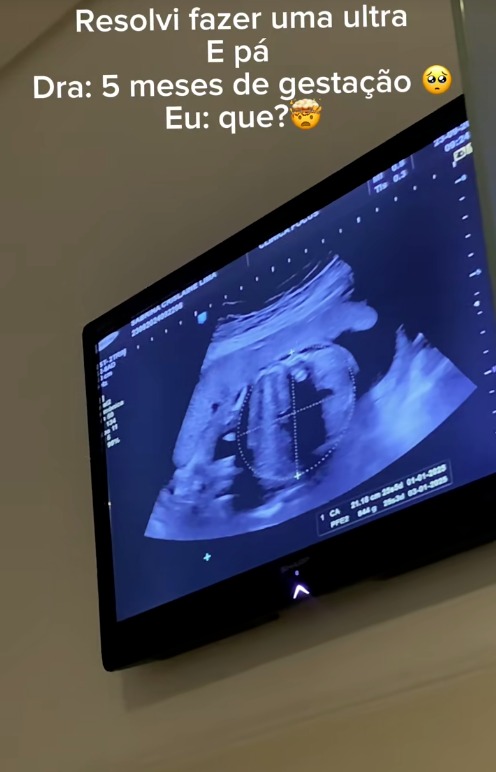

Sabrina Crislaine já estava no quinto mês de gestação quando descobriu que estava grávida. Aos 23 anos, a pernambucana de Palmares publicou em seu perfil nas redes sociais um vídeo em que compartilha como descobriu a gravidez, mesmo sem apresentar os sintomas habituais.

Em seu relato, a jovem afirmou ainda que sentia algo como uma "bolinha" na barriga toda vez que se deitava, mas não chegava a ser um incômodo; por isso, não desconfiou que poderia ser um sintoma da gravidez. No quinto mês, decidiu fazer um teste de gravidez e recebeu o resultado positivo. Ainda sem acreditar, decidiu fazer a ultrassom, ocasião em que descobriu que já estava gestante de quase 20 semanas, conforme mostrou em um dos vídeos.